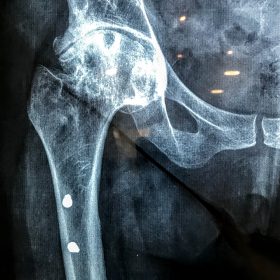

Σε αυτό το σημείο η Αρθροπλαστική Ισχίου αποτελεί μονόδρομο.

Παραδοσιακά οι αρθροπλαστικές ισχίου αποτελούνται από μια μεταλλική μπάλα – σφαίρα τοποθετημένη σε μια πλαστική κοιλότητα (κοτυλιαία πρόθεση).

Η πλαστική επιφάνεια στήριξης φθείρεται με την πάροδο του χρόνο, με ρυθμό μάλλον σχετιζόμενο με το επίπεδο δραστηριότητας του ατόμου. Αυτό έχει σαν επακόλουθο νεότεροι ασθενείς με μεγαλύτερο προσδόκιμο ζωής να έχουν αυξημένο ρίσκο αναγκαιότητας δεύτερης αρθροπλαστικής ισχίου (αναθεώρησης – Revision) επέμβαση που είναι πολυπλοκότερη και υπόκεινται σε υψηλότερο κίνδυνο επιπλοκών. Βάση των ανωτέρω, ιστορικά, η αρθροπλαστική ισχίου σπανίως εφαρμοζόταν σε ασθενείς κάτω των 60 ετών.

Χάρη στα νέα τεχνολογικά επιτεύγματα έχουν παραχθεί επιφάνειες στήριξης που ανταποκρίνονται σε μεγαλύτερα επίπεδα δραστηριότητας και αναμένεται να έχουν μεγαλύτερη διάρκεια ζωής. Αυτές οι καινούριες επιφάνειες στήριξης είναι συνήθως μέταλλο πάνω σε ειδικό σκληρότερο πλαστικό ή κεραμικό πάνω σε κεραμικό. Ως εκ τούτου, είναι τώρα πολύ πιο σύνηθες, νεότεροι ασθενείς να χειρουργούνται καθώς η πλειονότητα αυτών, που η αρθρίτιδα τους προκαλεί αφόρητους πόνους, επιλέγουν να έχουν ποιότητα ζωής από το να ζουν με τον πόνο.

Η αρθροπλαστική ισχίου αποτελεί μια αποτελεσματική επέμβαση αποκατάστασης και πρέπει να εφαρμόζεται μόνο όταν οι ασθενείς δεν είναι σε θέση να αντέξουν άλλο τον πόνο και την ανικανότητα και εφόσον τα πλεονεκτήματα καθώς και οι πιθανοί κίνδυνοι της μεθόδου έχουν εξηγηθεί πλήρως από το χειρουργό και έχουν κατανοηθεί από τον ασθενή.